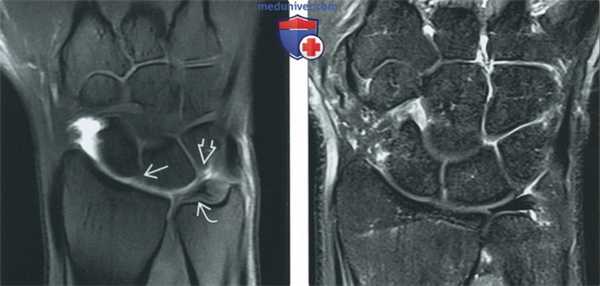

Применение артрографии при МРТ мелких суставов часто имеет преимущества. Выявление разрывов связок без смещения может быть затруднено без применения артрографии, даже при мощности томографа 3 Тс.

(Слева) Корональная Т1 FS МР-артрограмма: контраст заполняет лучезапястный сустав и подчеркивает нормальные лучезапястное и полулунно-трехгранное сочленения, а также треугольный фиброзно-хрящевой комплекс. Это наиболее точный метод подтверждения целостности связок.

(Справа) Корональная непрямая МР-артрограмма Т1 FS после внутривенного введения контрастного вещества: визуализируются усиленные за счет контраста связки проксимальной и дистальной поверхностей, контраст находится во всех отделах, что ограничивает возможность выявления дефекта связок.

Непрямая артрография не показана при исследовании лучезапястного сустава, так как контрастируются все отделы запястья. Это отменяет привычный диагностический критерий экстравазации контраста. Метод не применим в плотных суставах, таких как тазобедренный, где содержится недостаточное количество жидкости для выявления патологических изменений.